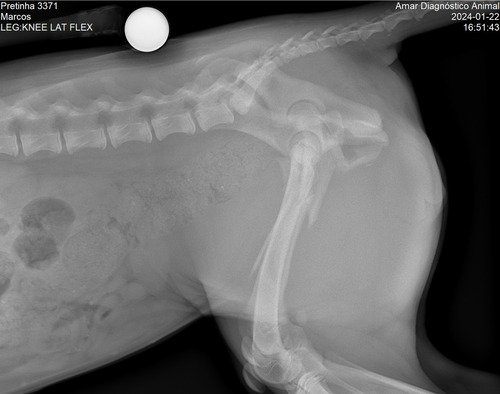

Meu nome é Flávia e moro aqui em Mogi Guaçu, interior de SP. No bairro onde eu moro infelizmente acontece muitos casos de abandono de animais, especialmente cachorros. Foi o caso dessa menininha linda da foto. Ela foi abandonada junto com sua mamãe e mais duas irmãzinhas. Infelizmente no último dia 21 de janeiro, a Belinha foi atropelada e o motorista fugiu sem prestar socorro. Depois de uma vaquinha comunitária e ajudas para as primeiras consultas e o Raio-X, foi constatada lesões na perninha direita, na bacia e baço, sendo então indicado um procedimento cirúrgico para que essa menininha amorosa possa continuar vivendo. Ainda não temos os custos finais para a cirurgia, mas certamente não sairá tão barato, pois além do procedimento também terá todo o processo do pós operatório. E é por isso que estamos abrindo essa Vakinha virtual para ajudar a custear a cirurgia e pós dela. Depois de recuperada, esperamos encontrar um lar lindo e feliz para ela, para sua irmãzinha e para sua mamãe. Nos ajude com qualquer valor. Caso consigamos algum excedente, vamos doar para ONGs que cuidam de animais aqui em nossa cidade. Que Deus os abençoe e guarde!!